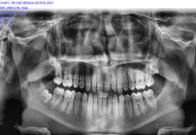

Before Treatment

OPG (Pre Treatment)

After Areatment

OPG (Post Treatment)

Case of full mouth rehabilitation All teeth extracted Upper single complete denture and lower Implant supported denture